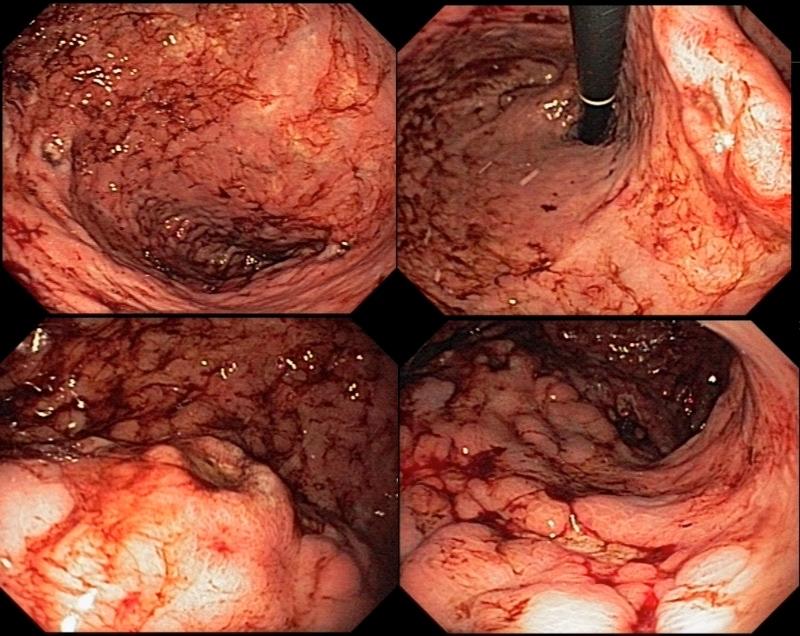

慢性肠系膜缺血导致的严重缺血性胃炎。

Severe ischemic gastritis caused by chronic mesenteric ischemia.

Ischemic gastritis is a rare illness caused by localized or systemic vascular insufficiency. This condition is rarely seen in medical practice due to the vast arterial collateral blood supply to the stomach through the celiac trunk and superior mesenteric artery and also because other etiologies are much more frequent. The classic presentation of chronic ischemia is comprises the triad of postprandial pain, weight loss, and abdominal bruit. Intervention is indicated in symptomatic patients and endovascular treatment is an alternative to surgery in patients with high comorbidity that offers good results. We report a case of a 71-year-old female patient with severe ischemic gastritis with ulcers and bleeding caused by chronic mesenteric ischemia with occlusion of the celiac trunk and inferior mesenteric artery and critical stenosis of the superior mesenteric artery. The diagnosis was confirmed by imaging, and the patient underwent endovascular treatment. This is a rare condition that is difficult to diagnose and treat and a multidisciplinary team is needed for proper management.

缺血性胃炎是一种由局部或全身血管供血不足引起的罕见疾病。由于通过腹腔干和肠系膜上动脉为胃提供了丰富的动脉侧支血液供应,而且其他病因更为常见,这种情况在医疗实践中很少见。慢性缺血的典型表现包括餐后疼痛、体重减轻和腹部血管杂音三联征。有症状的患者需要进行干预,对于合并症高的患者,血管内治疗是手术的替代方法,效果良好。我们报告一例71岁女性患者,患有严重的缺血性胃炎,伴有溃疡和出血,由慢性肠系膜缺血导致腹腔干和肠系膜下动脉闭塞以及肠系膜上动脉严重狭窄引起。通过影像学检查确诊,患者接受了血管内治疗。这是一种罕见的疾病,难以诊断和治疗,需要多学科团队进行妥善管理。